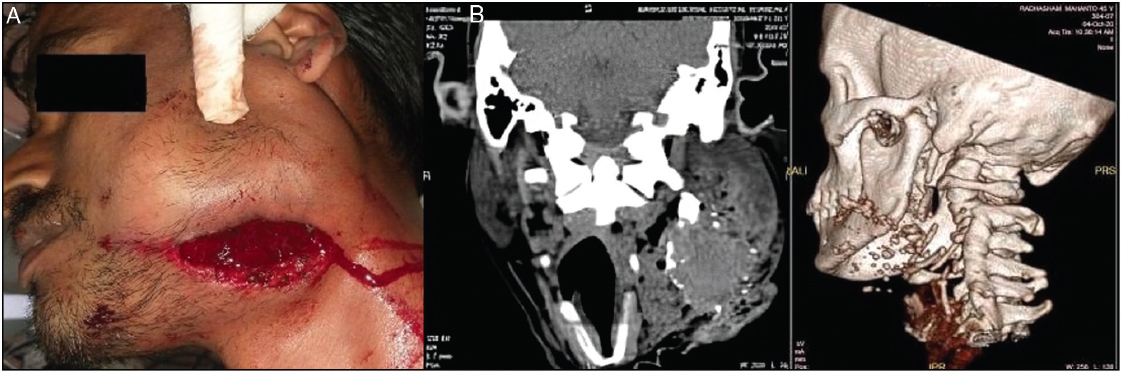

A 45-year-old conscious and well-oriented male was presented to the emergency department with painful swelling in the left cheek and a wound dressing in the left submandibular region, which had been in place for two hours [Figure 1]. The patient exhibited positive responsiveness to verbal commands and initially received first aid treatment at a rural health facility. The patient demonstrated positive responsiveness to verbal commands and initially received first aid treatment at a rural health facility. The patient’s medical history revealed that the trauma was a result of contact with a fragment of a grinding wheel rotating at high speed. Furthermore, upon extraoral examination, a laceration measuring approximately 4 × 2 cm was identified in the left body-angle region, affecting the skin and the underlying platysma muscle. A substantial clot and green grinding disc fragments were observed within the wound. The patient exhibited limited ability to rotate his head to the left. Intraorally, no discrepancies or instability in occlusion were noted, and there was no active bleeding at the injury site. A computed tomography (CT) scan was advised to the patient. Skull base and vertebrae fracture were ruled out. It revealed multiple radiopaque foreign objects scattered all over the submandibular and the retromandibular region, with the largest piece (2.2 × 0.5 cm) presented posterior to the left ramus of the mandible inferior to the left parotid gland. It also revealed a hematoma of 7 × 5 cm in size about the left mandible body and ramus region which corroborated the clinical finding [Figure 1]. The case was taken as an emergency. Wound debridement under GA was the treatment plan decided. The incision was made by widening the existing laceration present extraorally. The hematoma was carefully removed with the help of gauze. Foreign bodies were visualized after the hematoma removal, especially the ones present in the retromandibular region. The wound was thoroughly explored, and disc fragments were removed. The larger piece was removed using a curved artery taking care not to damage any adjacent vital structures [Figure 2]. There was a presence of powder of the foreign body which was cleared out using copious saline irrigation. Closure was done in multiple layers using 3-0 vicryl sutures. Aggressive pre- and post-operative antibiotic coverage was given. Extraoral pressure bandage was given to obliterate any dead space. The post-operative period was uneventful. The patient was followed up for the next 3 months with no further complaints [Figure 3].

Figure 1: (A) Pre-operative picture of the patient. (B) Pre-operative CT scan